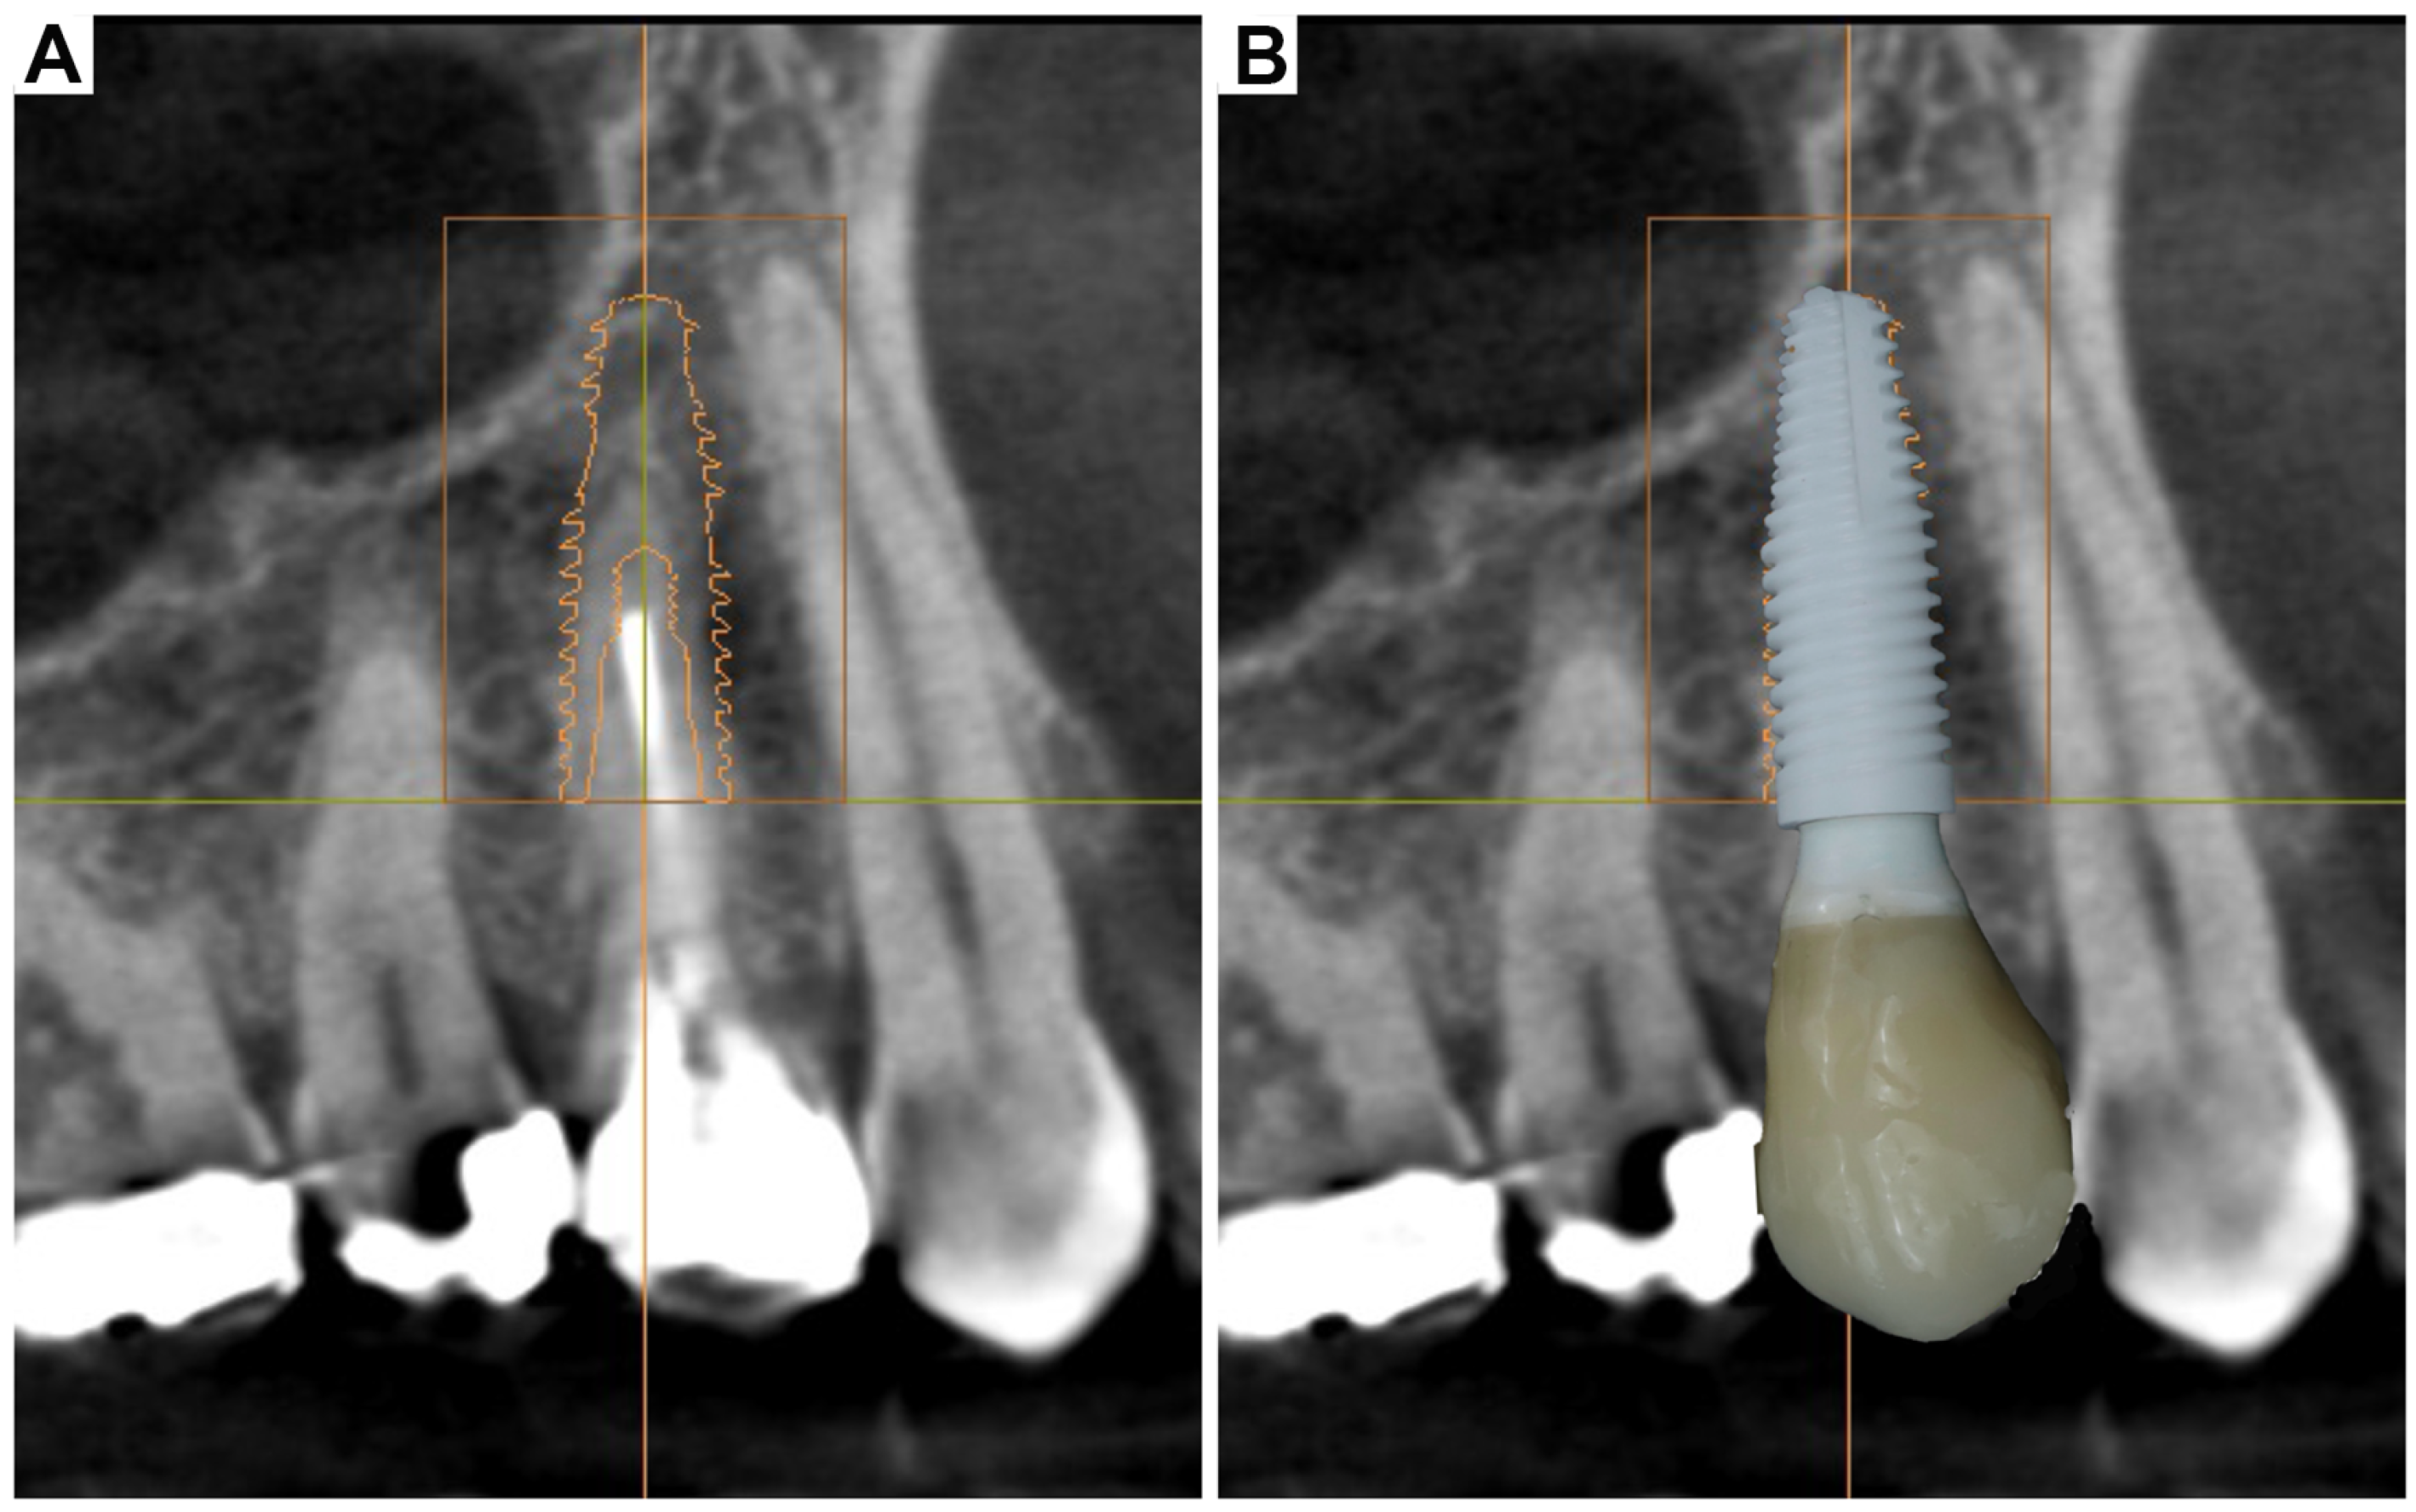

3. Clinical Cases Presentation of Advanced Implant Surgeries

3.1. Case Report-1